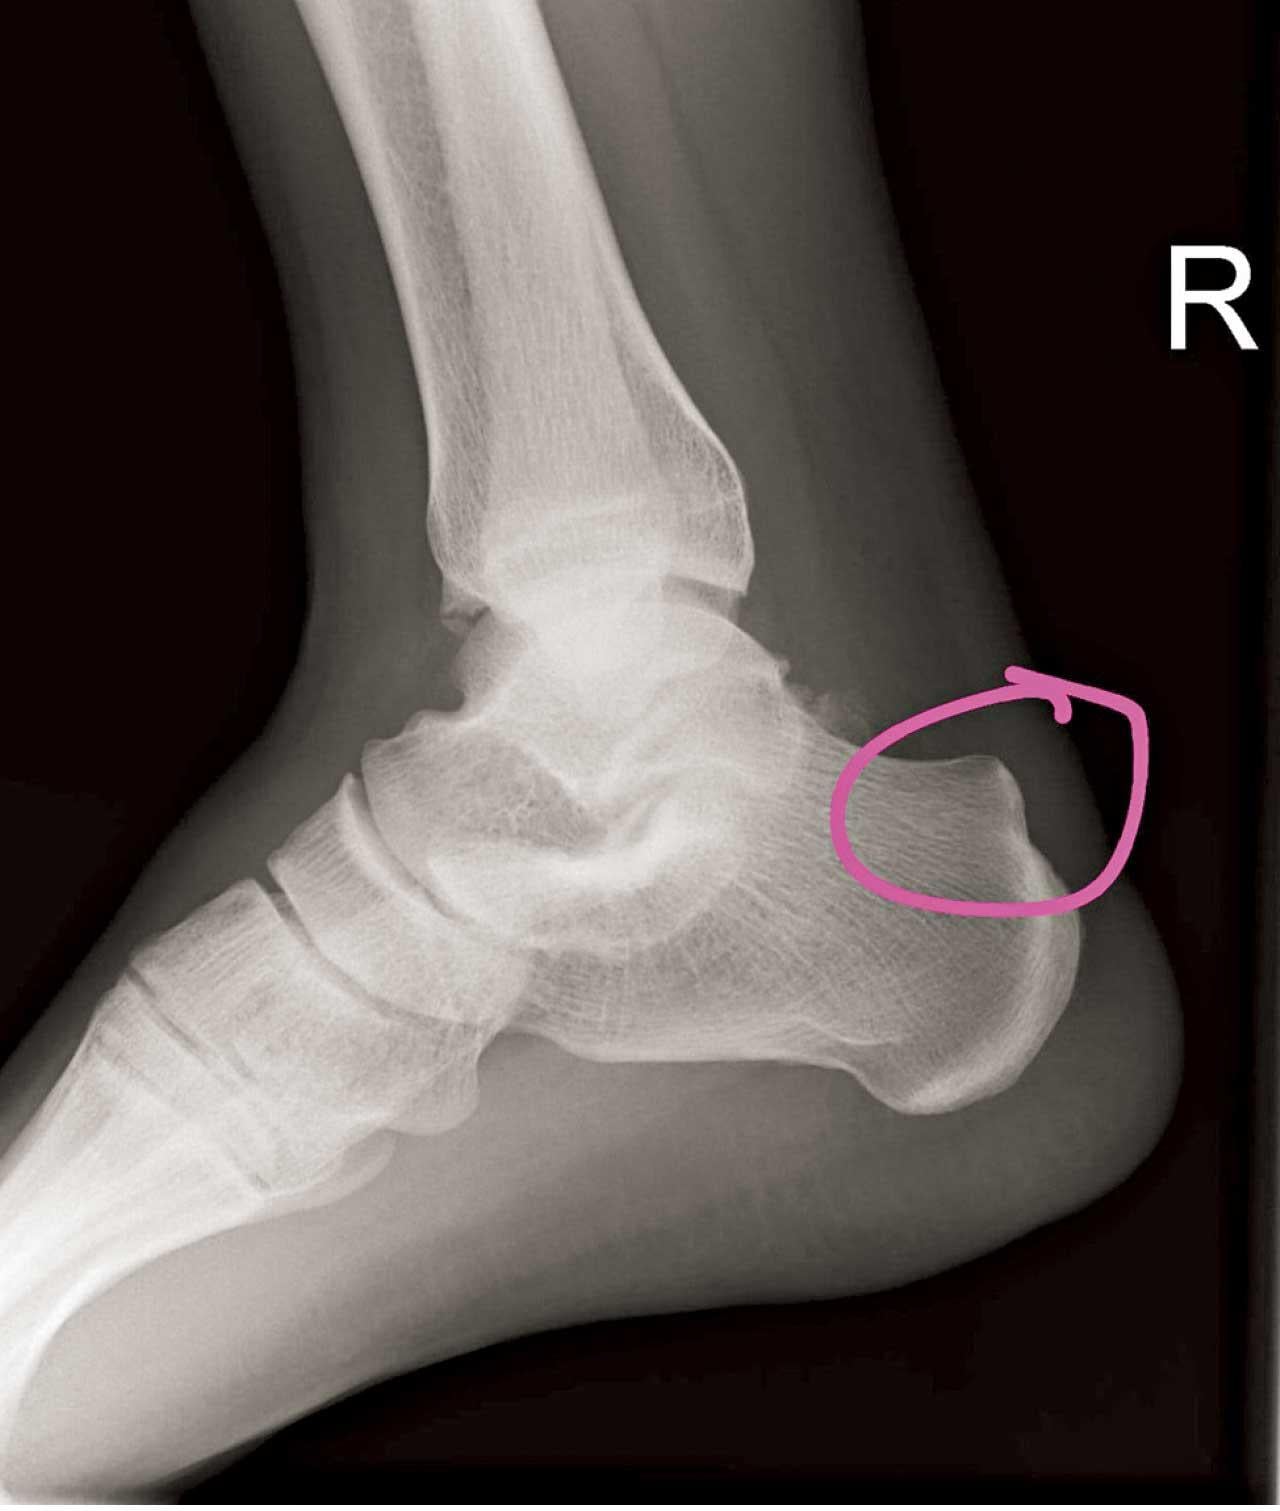

哈格倫氏變形是指腳跟骨有骨質增生,外觀上於腳後跟外側上方明顯隆起。凌家健指此症成因並不完全明確,或與家族病史有關係,而長跑人士、多做運動、足弓較高的人都會有較高風險患上哈格倫氏變形,「一個較特別的情況是,即使患者的腳跟骨都有明顯凸起增生,但只有部分人感痛楚,另一部分則完全沒有病徵,仍未了解為何有此現象。」

哈格倫氏變形的腳跟骨上方會凸起,或引致痛楚。